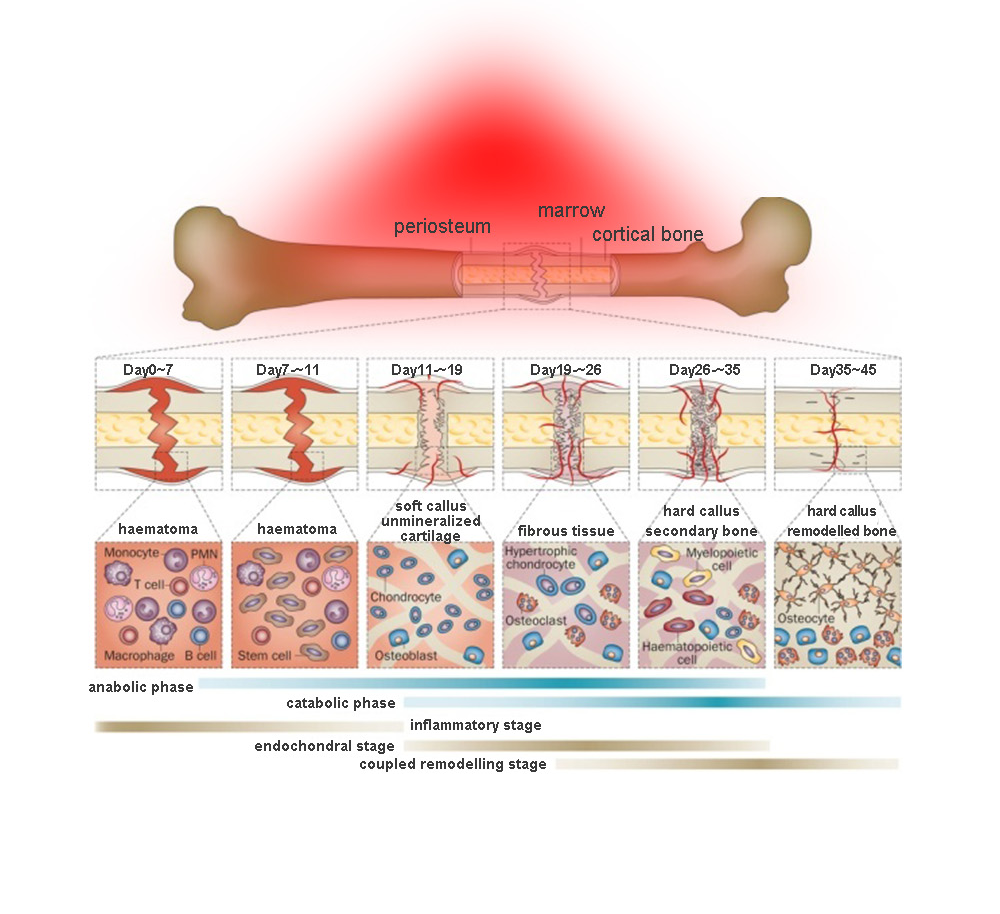

Red light therapy is also known as low-level laser therapy (LLLT). It uses low energy light emitting diodes (LEDs) or lasers as an alternative therapy for pain relief, or to promote good cell functions.

The principle of red light therapy can be thought of as like a human version of the way plants photosynthesize. It is thought that certain wavelengths of light can enhance the functioning of mitochondria, which are the organelles in a cell which take in nutrients and break them down to create energy molecules for the cell. By enhancing the cellular respiration, it will improve the functioning of the whole cell.